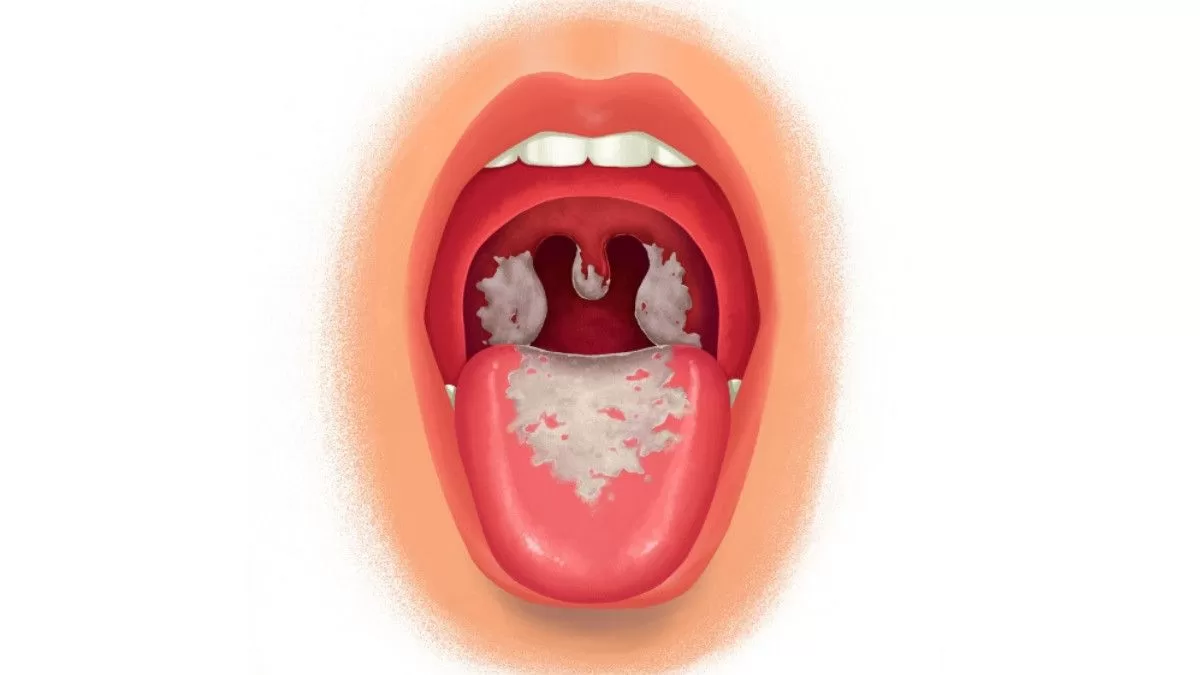

3. Faringitis dan Laringitis

Faringitis merupakan peradangan pada faring sehingga timbul rasa nyeri pada waktu menelan ataupun kerongkongan terasa kering. Gangguan ini disebabkan oleh infeksi bakteri atau virus dan dapat juga disebabkan terlalu banyak merokok. Bakteri yang biasa menyerang penyakit ini adalah Streptococcus pharyngitis.

Laringitis mengakibatkan penderita serak atau kehilangan suara. Penyebab laringintis antara lain karena infeksi, terlalu banyak merokok, minum alkohol, dan terlalu banyak serak.

7. Dipteri

Dipteri merupakan penyakit infeksi yang disebabkan oleh bakteri Corynebacterium diphterial yang dapat menimbulkan penyumbatan pada rongga faring maupun laring oleh lendir yang dihasilkan oleh bateri tersebut.